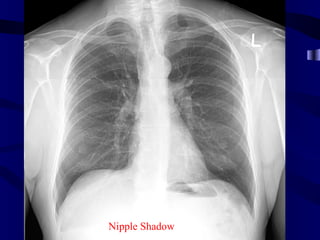

Nipple Shadow

Chest imaging